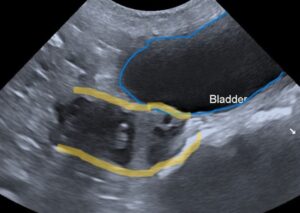

青で囲っている部位が膀胱(おしっこが黒く映っています)

黄色の線が子宮になります(子宮内の液体が黒く映っています)

※超音波画像では液体が黒く映ります。

腹部超音波検査:子宮内膜の肥厚と子宮内の液体貯留を確認。さらに子宮体部に複数の嚢胞状病変を認めました。